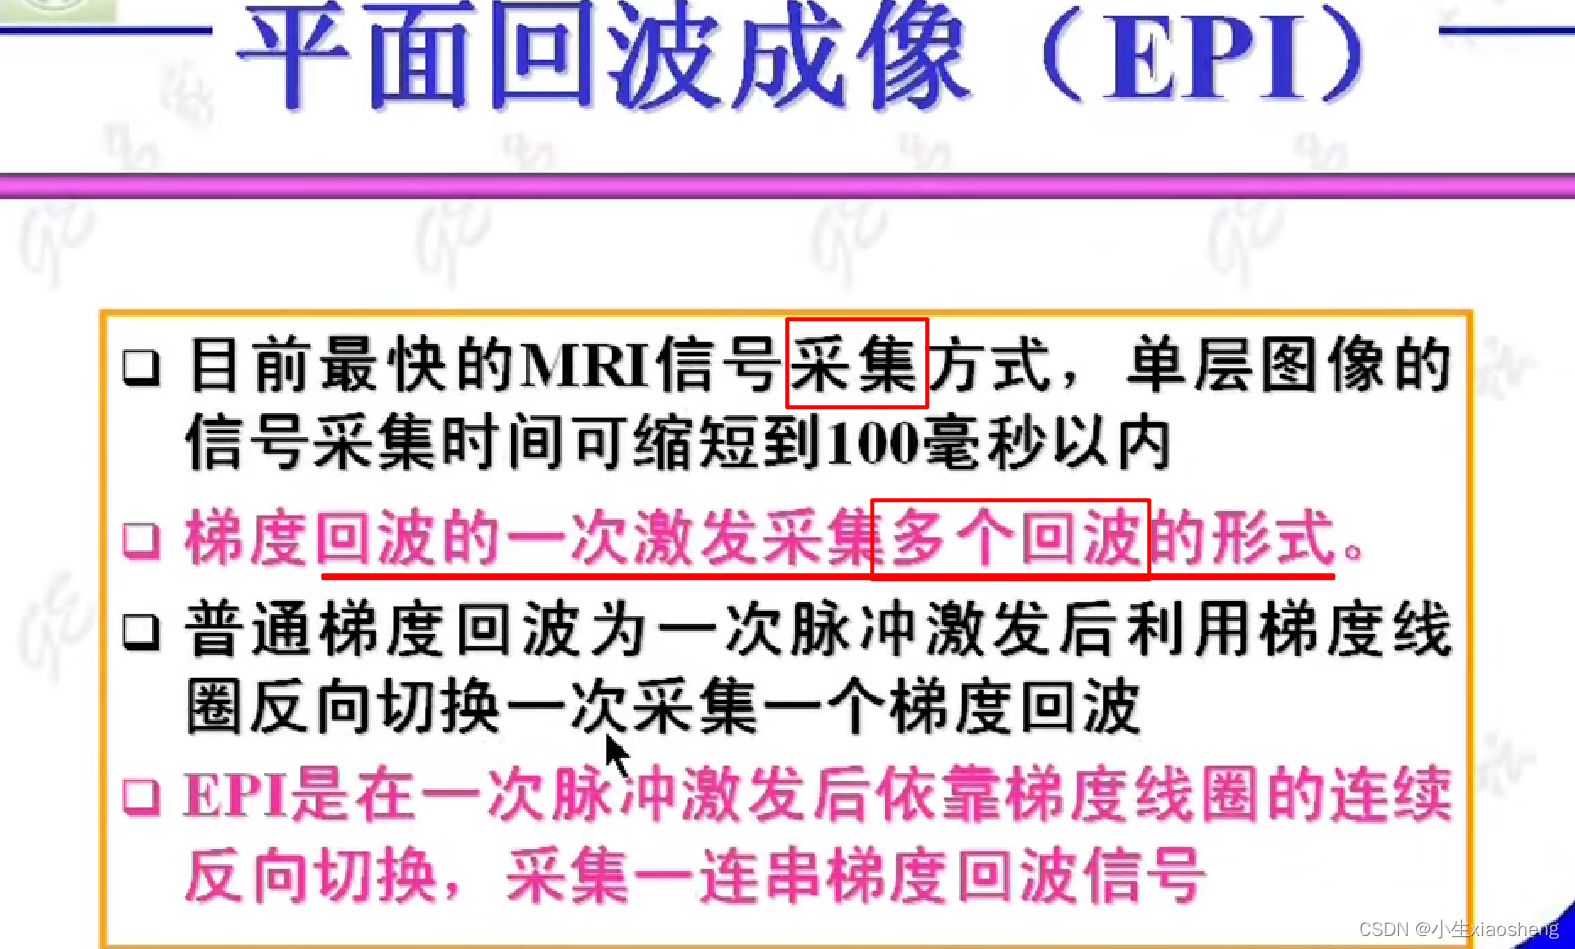

七、EPI序列

当然连续时不会像单次激发那样把整个K空间填满,还是需要经过几个90度脉冲。

自旋回波--90度和180度填充K空间;反转恢复--在自旋的基础上两边加180度;梯度回波--消除每次脉冲留下的影响,以及波的次数;propeller==》K空间填充技术和FSE或FIR结合用于减少运行伪影;EPI==》采集方式,一次激发采集多个回波的形式但与单次不一样;PRESTO和GRASE==》前面几种的一种结合形成新的。